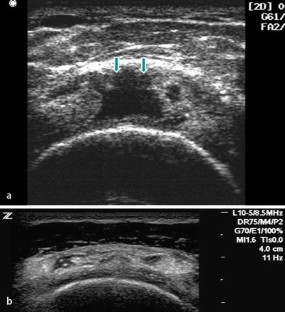

Bildgebende Verfahren bei Rotatorenmanschettendefekten der Schulter

Imaging in evaluating rotator cuff tears

Vor der Indikation zur bildgebenden Diagnostik steht die klinisch begründete Verdachtsdiagnose. Die Basis der bildgebenden Diagnostik bei Rotatorenmanschettendefekten bilden die konventionelle Röntgendiagnostik und die Sonographie. Für spezielle Fragestellungen bietet sich die Kernspintomographie an. Sehnentotaldefekte können sowohl im MRT als auch mit der Sonographie mit großer Sicherheit erkannt werden. Die Diagnostik von Partialdefekten der Manschette ist weiterhin verbesserungswürdig. Die Sicherheit des nativen MRT in der Diagnostik von Partialdefekten kann sowohl durch die indirekte als auch die direkte MR-Arthrographie deutlich gesteigert werden. Nur die Sonographie bietet bislang die Möglichkeit, im Echtzeitverfahren am bewegten Gelenk zu untersuchen. Mit der dynamischen Muskelsonographie sind zusätzliche Möglichkeiten gegeben, die Funktionsfähigkeit der Muskulatur zu erfassen. Der Einsatz der MRT als Screeningmethode sollte unterbleiben, da mit ihrer Hilfe keine therapeutisch relevanten Informationen gewonnen werden.

Diagnostic imaging in a patient with shoulder pain should be used only after a comprehensive clinical evaluation of the shoulder. X-ray and ultrasonography are the basic diagnostic tools; computed tomography and magnetic resonance imaging (MRI) should be used only with certain indications. Ultrasonography and MRI have comparable accuracy for identifying and measuring full-thickness rotator cuff tears, but the accuracy for identifying partial-thickness still needs to be improved. MR arthrography has significantly improved sensitivity and specificity for partial-thickness tears of the cuff. Only ultrasound provides a real-time examination tool during shoulder movements. Moreover, dynamic ultrasonography can assess the contraction patterns of the supraspinatus and infraspinatus muscles, which may improve decision making in the treatment of shoulder diseases. In depicting fatty atrophy of the supraspinatus and infraspinatus muscles, MRI remains the reference standard. MRI should not be used as a diagnostic screening tool in patients with chronic shoulder pain because it does not appear to significantly affect treatment or outcome.